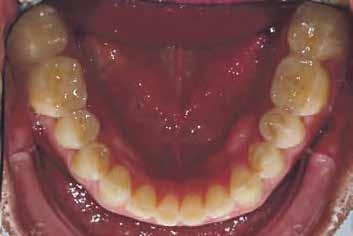

A felső és az alsó állkapocsról történt szituációs lenyomatokat kiöntötték, a laboratóriumi szkennerrel digitalizálták (3Shape), és az adatokat a Digital Denture szoftverbe importálták. A szoftver SR IvoBase® CAD és SR Vivodent® CAD Multi kombinációjával - fogszínű korongokkal - lehetővé teszi digitális protézisek automatizált gyártását.

Ideiglenes protézis CAD-konstrukcióban

Az ideiglenes fogsor elkészítéséhez a még meglévő fogakat törölni kellett a virtuális modellről (3. ábra). Ehhez a szoftver megfelelő eszközöket biztosít. A modellanalízis közben a szoftver lépésről lépésre vezet minket. Az anatómiai jellemzőket megjelöljük és a fogsor kiterjesztésének paramétereit rögzítjük (4. ábra). Az állkapocsviszony meghatározása alapján a függőlegest 5,5 mm-rel megemeltük (5. a ábra). A Digital Denture Full Arch könyvtár segítségével megtörtént a megfelelő fogforma kiválasztása (Phonares® II B71-L50-N3)